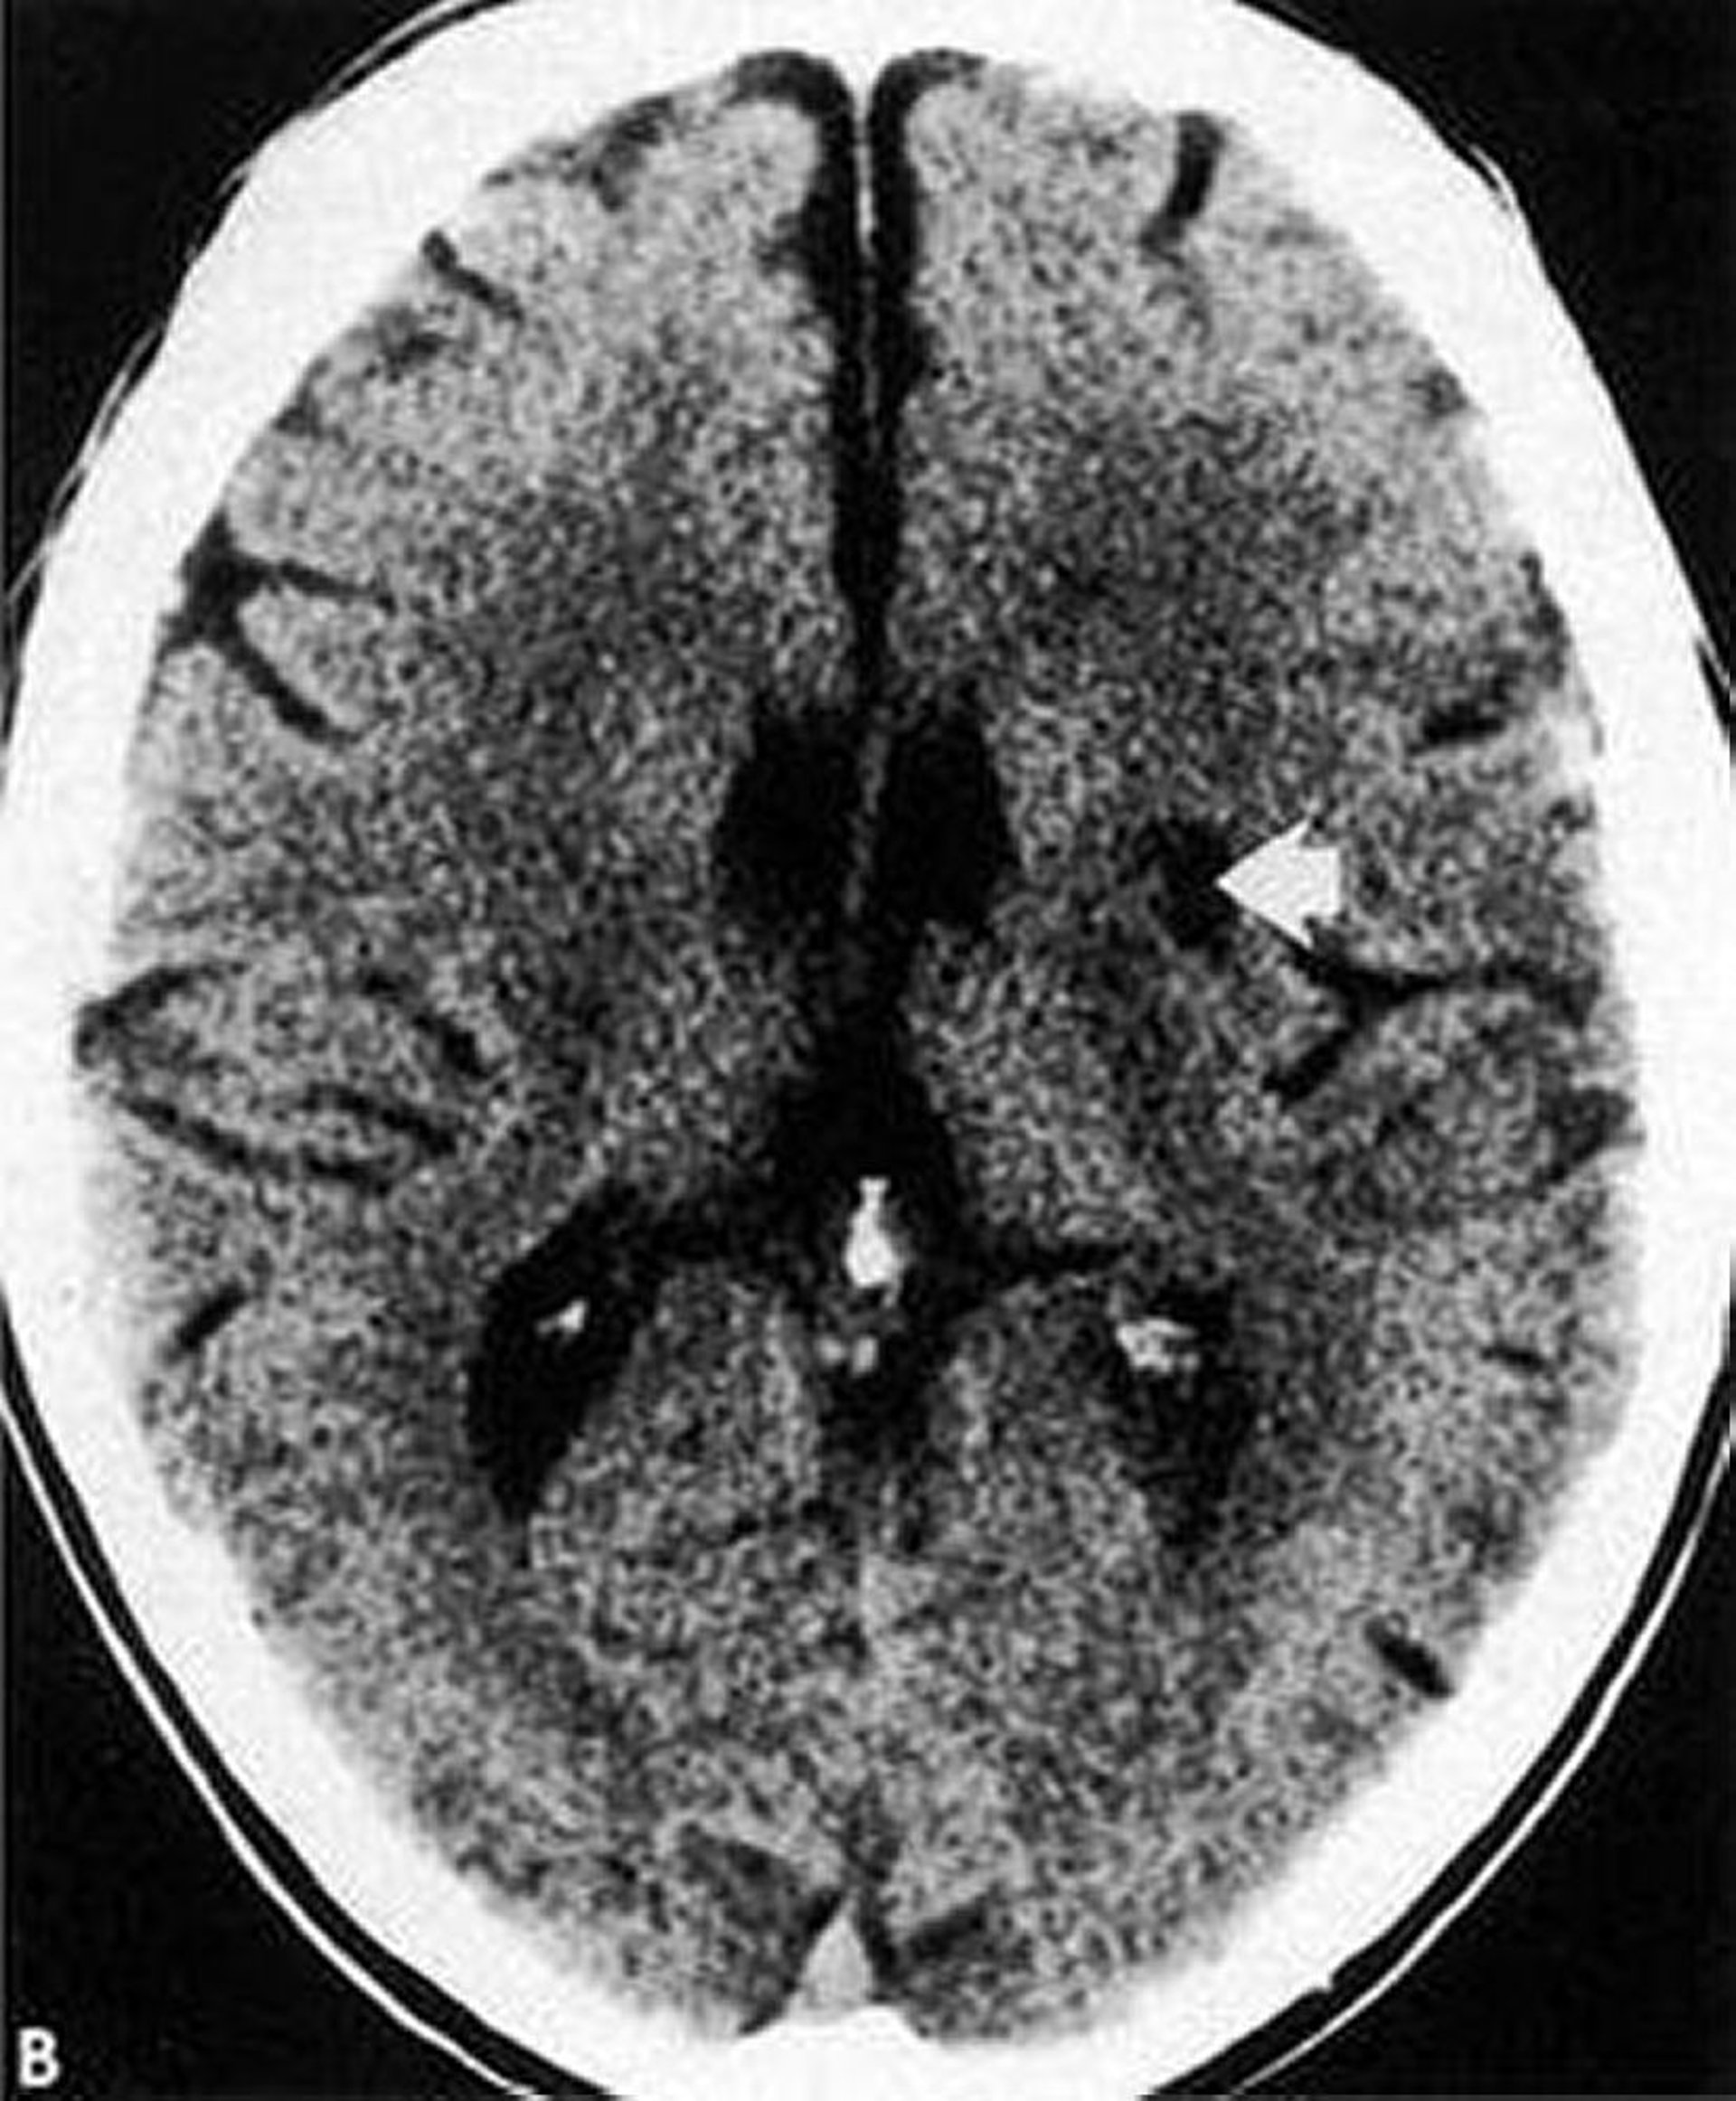

ラクナ梗塞

このCT画像では,基底核にラクナ梗塞による境界明瞭な低吸収域(矢印)がみられる。